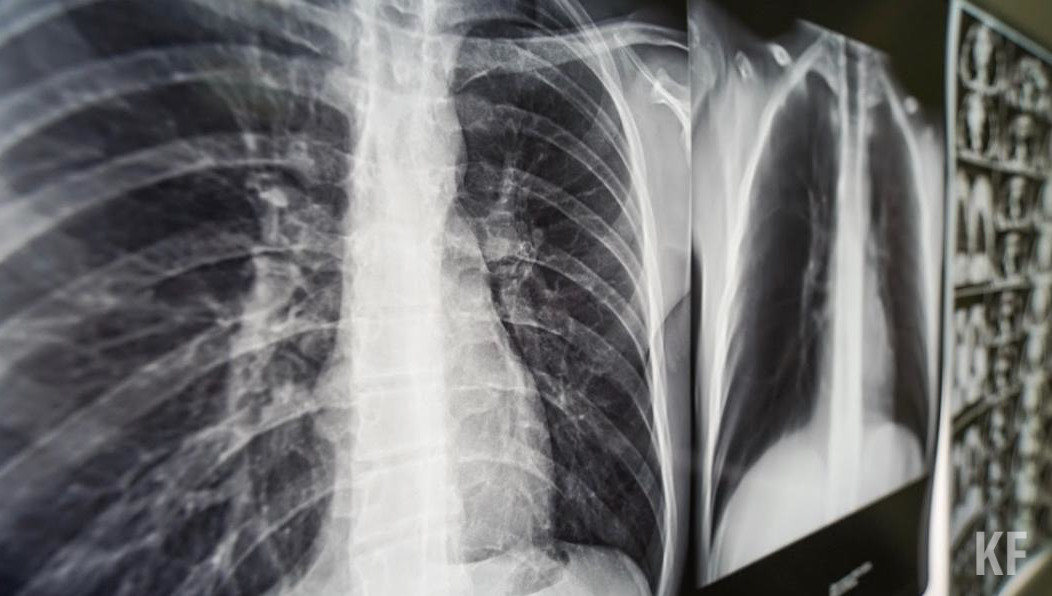

— Электронные сигареты вызывают никотиновую зависимость. Вещества, входящие в состав аэрозолей электронных сигарет, в частности вкусовые добавки и ароматизаторы, оказывают пагубное воздействие на ткани бронхов и легких и могут стать причиной поражения легких, связанных с вейпингом — EVALI. Это заболевание, распространенное среди молодых людей в США. Появление EVALI — результат эпидемии потребления электронных сигарет в Америке. У нас пока нет эпидемии, но она не за горами, если не регулировать распространение и потребление электронных сигарет и не принимать меры», — предупредила специалист.